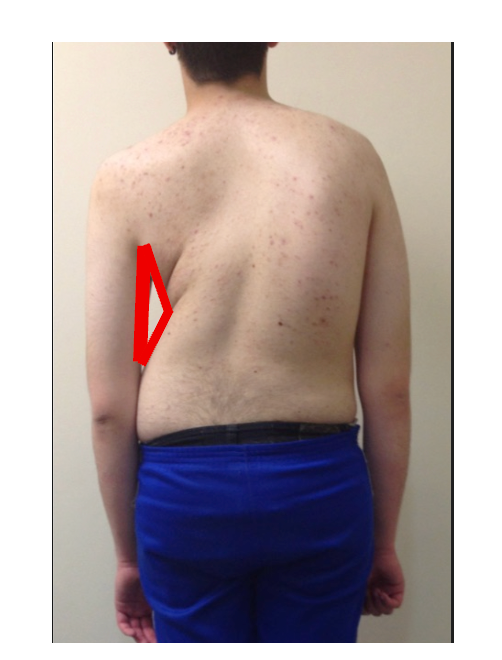

A deformidade causada pela inclinação e rotação das vértebras pode tornar-se perceptível ao observar a pessoa, principalmente pelas costas. Este é o principal sinal da escoliose e sua intensidade varia conforme:

- o tamanho da curva (ângulo de Cobb),

- o número de vértebras acometidas,

- e o grau de rotação vertebral.

Quanto maior a magnitude da curva, maior tende a ser a percepção da deformidade.

A escoliose pode ser inicialmente percebida pela observação do tronco. Muitas vezes, a mãe, o pai ou outro familiar nota uma assimetria, como diferença entre os lados do corpo em relação aos braços, à cintura ou aos ombros. Em alguns casos, observa-se também uma proeminência das costelas, próxima a um osso chamado escápula.

Desse modo, durante a avaliação médica, o ortopedista observa esses sinais e realiza um exame físico específico chamado Teste de Adams. Nesse teste, o paciente inclina o tronco para frente, flexionando a coluna torácica e lombar, sem dobrar os joelhos. Nos casos em que existe escoliose estrutural, torna-se visível uma elevação assimétrica das costelas, conhecida como giba costal.